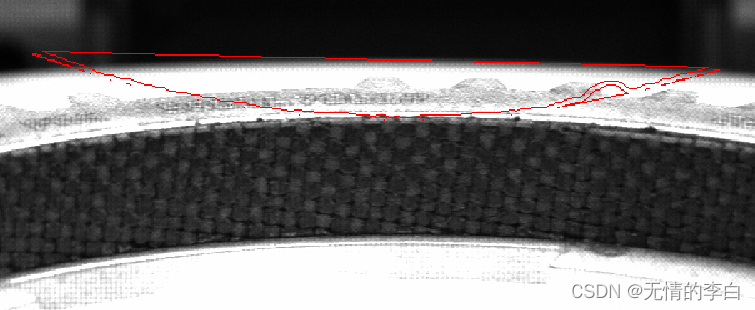

gen_region_polygon (Region_xbj, rows_zb, col_zb)

dilation_circle (Region_xbj, RegionDilation_xbj, 4)

shape_trans (Region_xbj, RegionTrans_xbj, 'convex')

difference (RegionTrans_xbj, RegionDilation_xbj, RegionDifference_xbj)

opening_circle (RegionDifference_xbj, RegionDifference_xbj, 1.5)

connection (RegionDifference_xbj, ConnectedRegions_xbj)